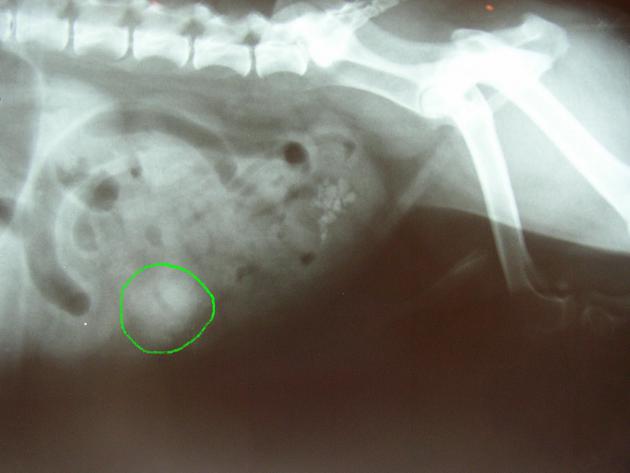

– La présence de certains corps étrangers peut être suspectée voire directement révélée par une radiographie simple: une dilatation de l’estomac et la présence d’air sur une radiographie abdominale de lapin feront très fortement suspecter la présence de trichobézoards tandis que des objets métalliques ou des os seront directement visibles sur le cliché radiographique de l’abdomen d’un chien.

en vert: corps étranger dans l’abdomen d’un chien (il s’agissait d’un morceau de caoutchouc)

(la radiographie révèle également la présence de calculs dans la vessie)